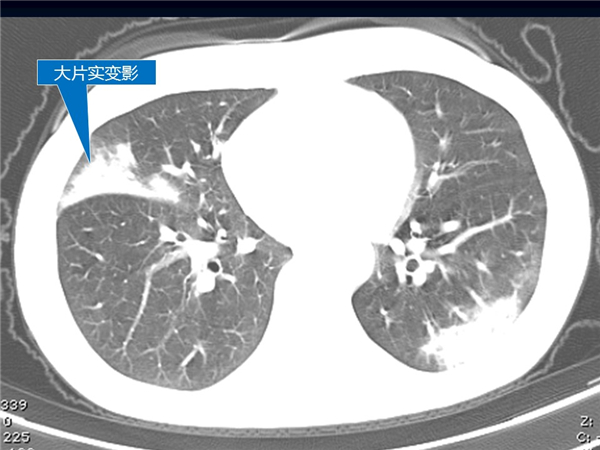

【病例分享】新型冠狀病毒感染肺部CT影像4例(常德市第一人民醫(yī)院)